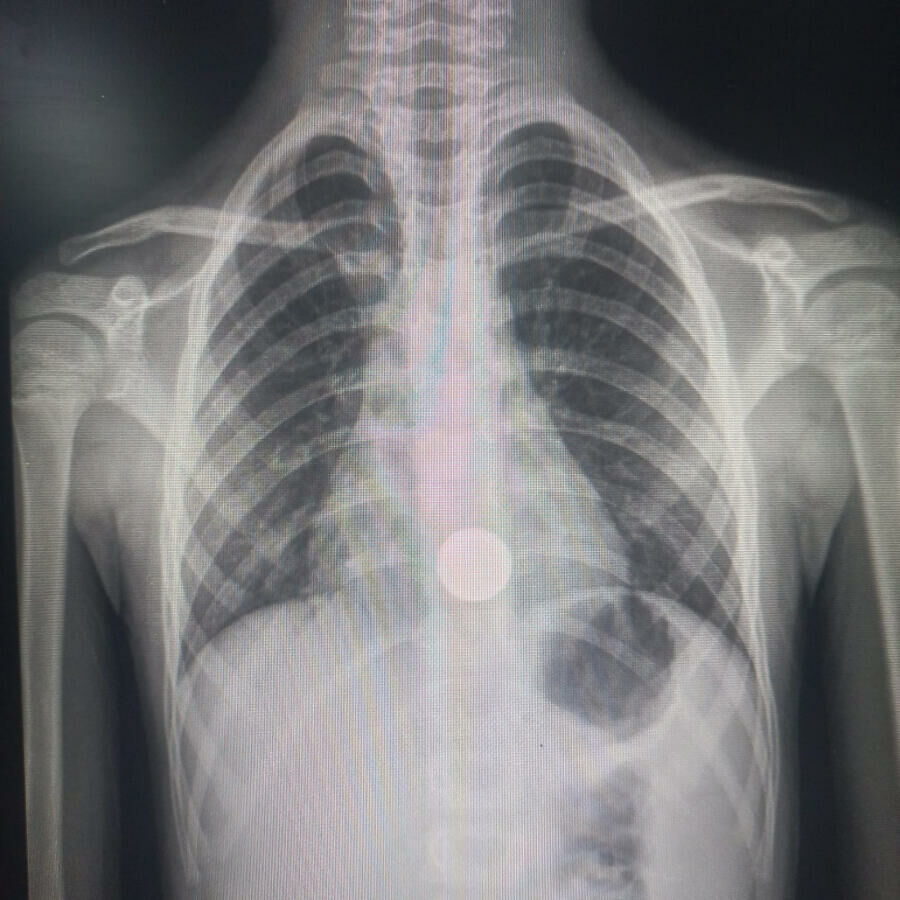

Após avaliação da equipe de saúde, o menino foi transferido para a Capital, onde passou por exames mais detalhados. O raio-x confirmou que a moeda está alojada na região do esôfago, o que exige procedimento médico para a retirada do objeto.

Inicialmente, o raio-x indicava a presença de uma moeda na região do esôfago. No entanto, durante o procedimento de retirada por meio de endoscopia, realizado no Hospital Regional, os médicos constataram que, na verdade, haviam duas moedas: uma de R$ 0,50 e outra de R$ 0,10.